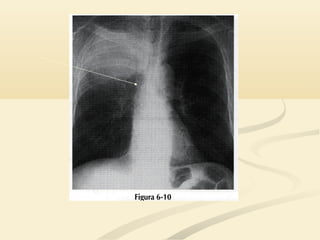

 La consolidación del LSI borrará la aurícula izquierda,La consolidación del LSI borrará la aurícula izquierda,

el botón aórtico y el mediastino anterior y medioel botón aórtico y el mediastino anterior y medio..

 La consolidacióndel LSI borrará la aurícula izquierda,La consolidación del LSI borrará la aurícula izquierda, el botón aórtico y el mediastino anterior y medioel botón aórtico y el mediastino anterior y medio..